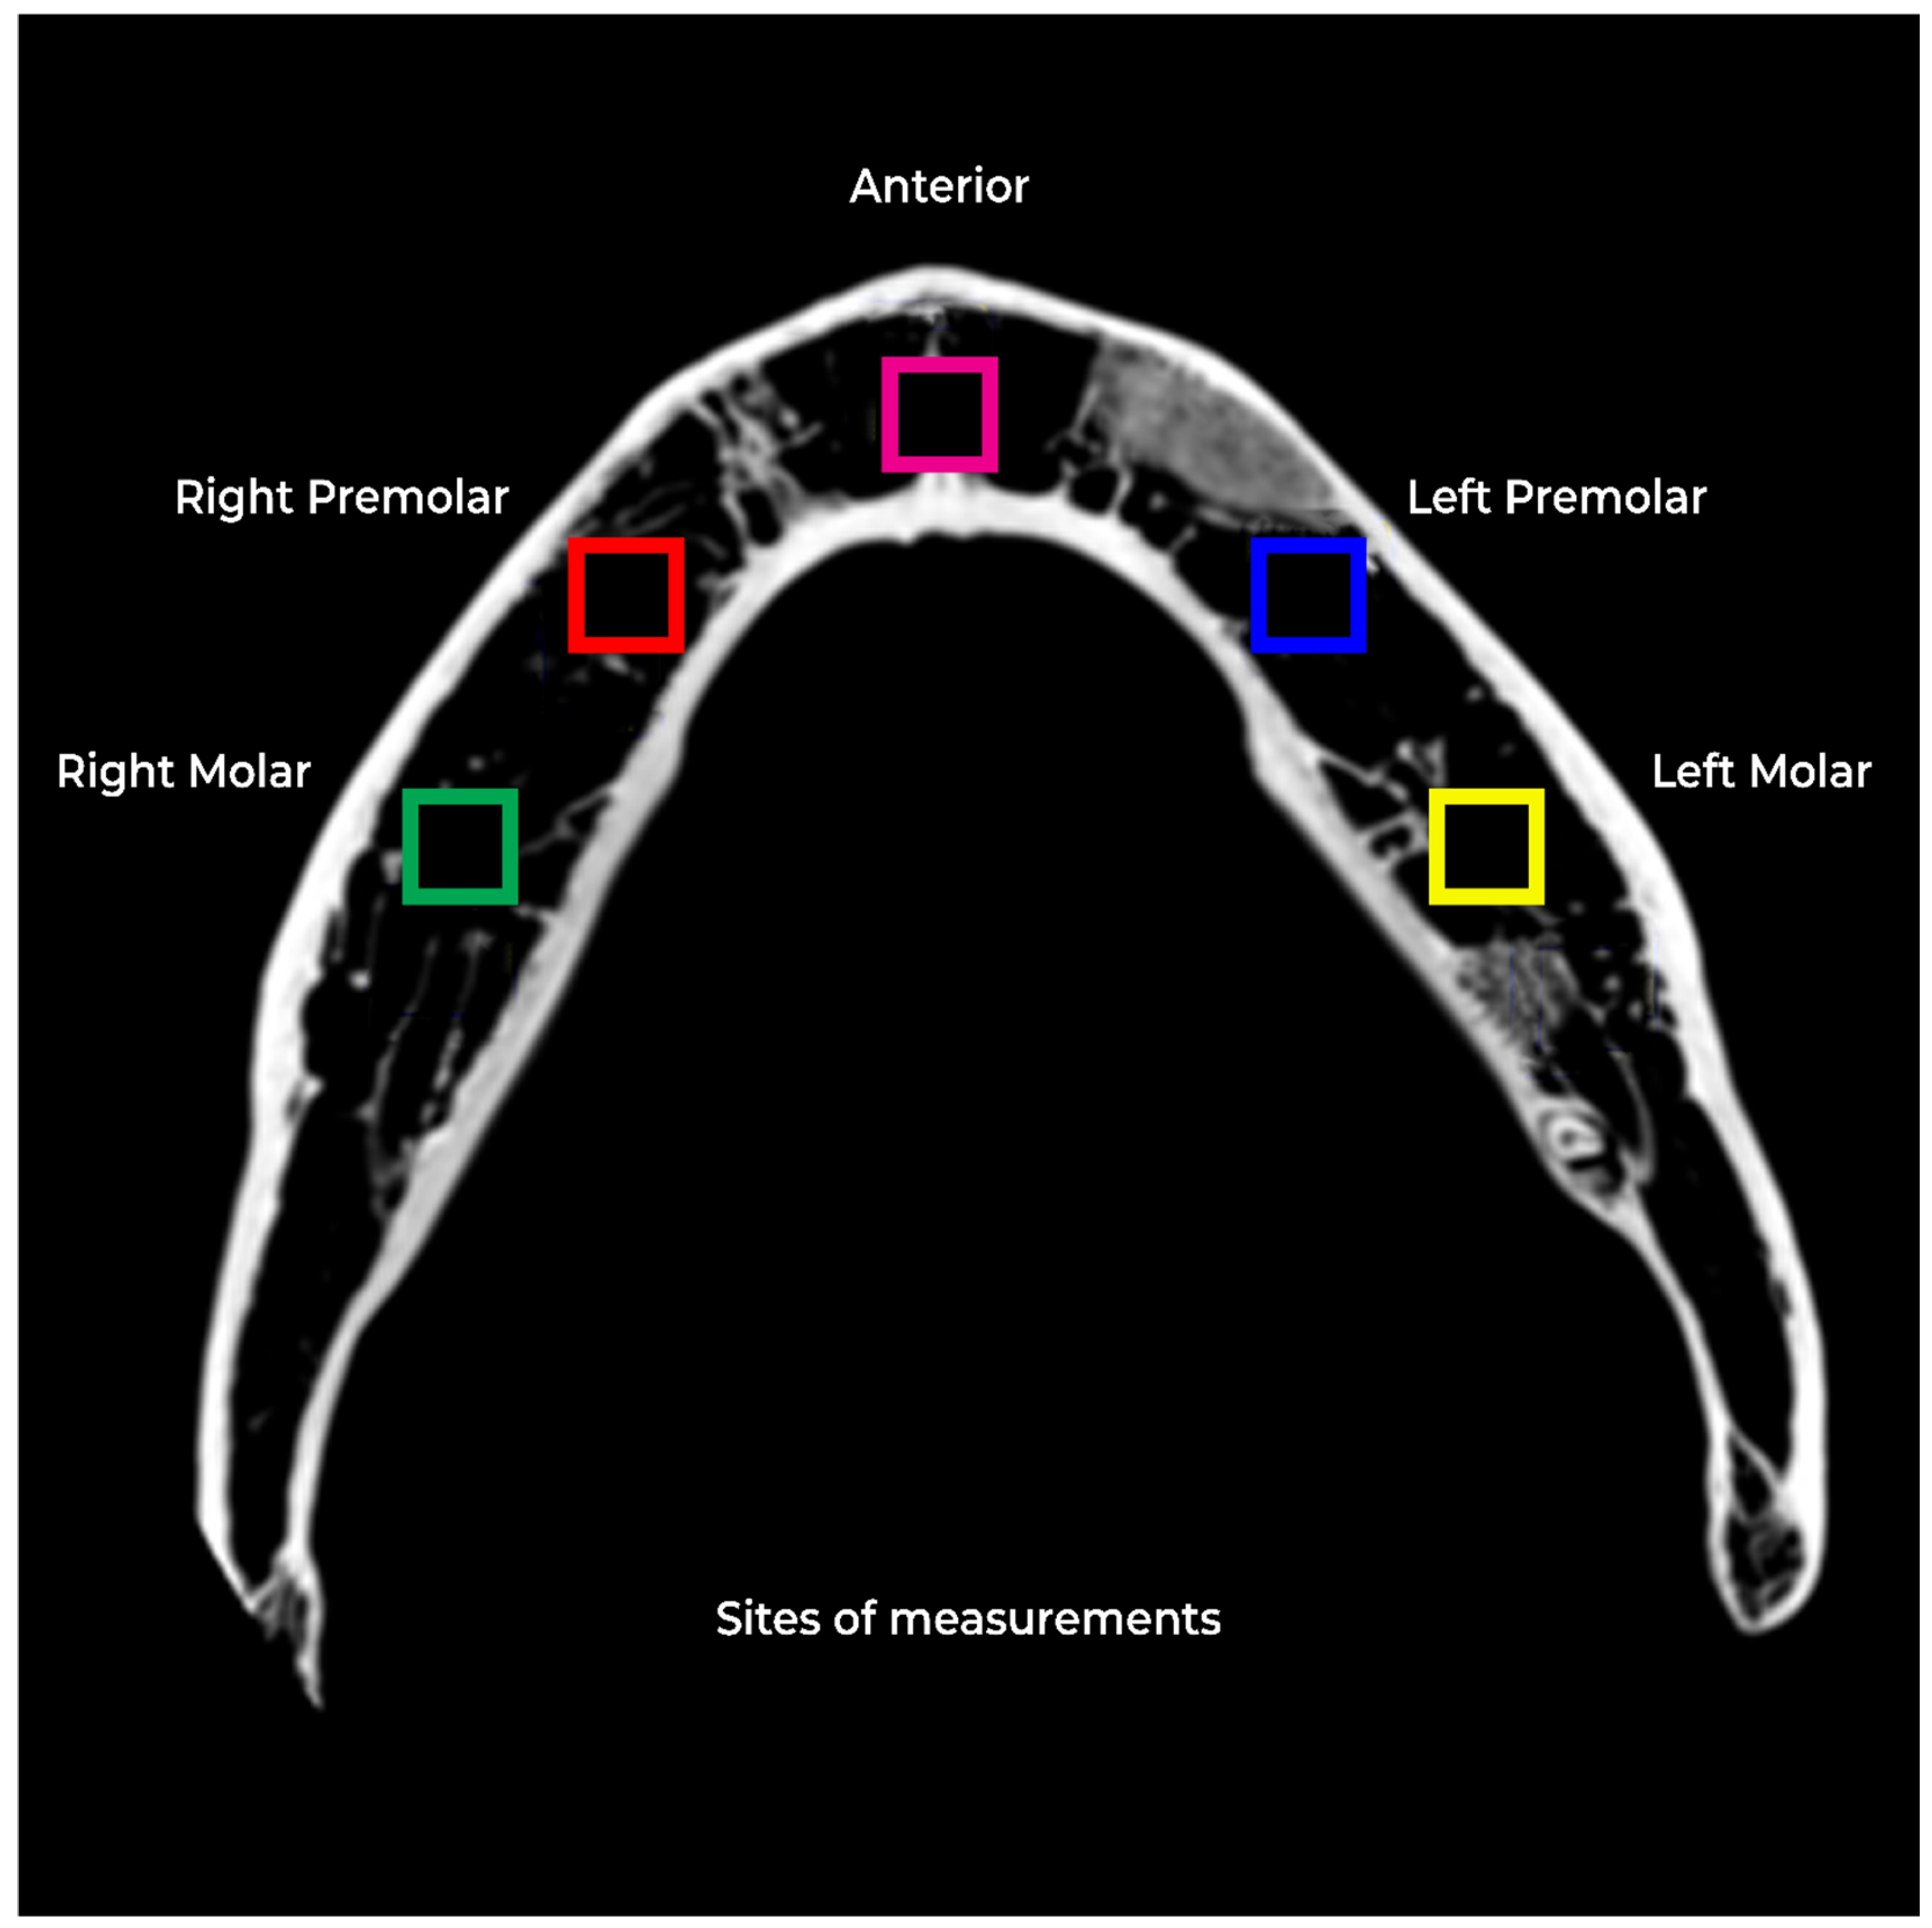

2. Materials and Methods